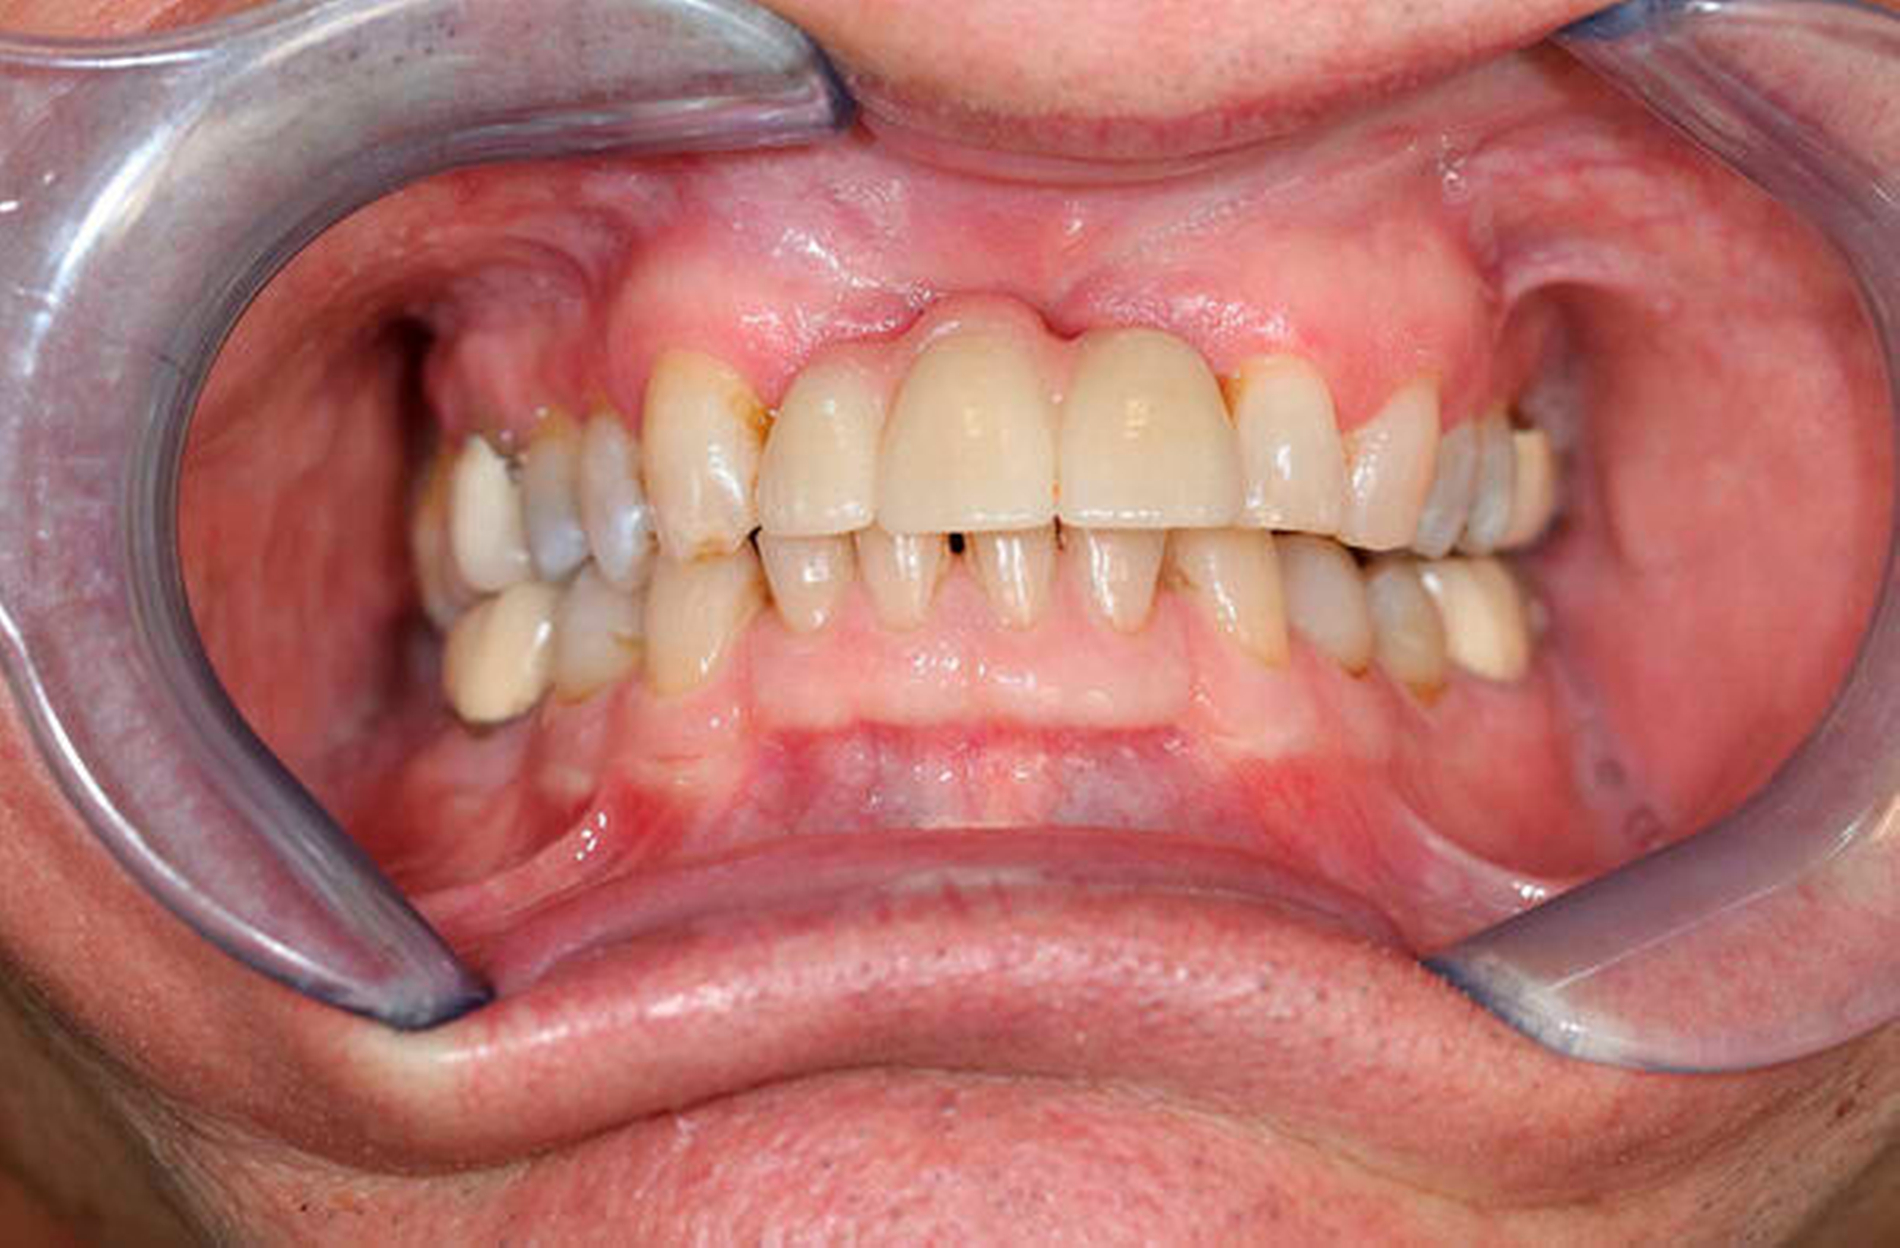

Anschließend wurde zur Ausbreitungsdiagnostik eine Magnetresonanztomografie (MRT) der Kopf-Hals-Weichteile mit Kontrastmittel durchgeführt (Abbildung 2). Hierbei kam eine malignomsuspekte Raumforderung im Oberkiefer im Bereich der regiones 11 bis 21 zur Darstellung, metastasensuspekte Auffälligkeiten der Halslymphknoten konnten nicht ausgemacht werden. Nach Besprechung des Falles in der interdisziplinären Tumorkonferenz wurde der Befund lokal mit Sicherheitsabstand in toto exzidiert und die mit der Raumforderung kommunizierenden Zähne 12, 11 und 21 extrahiert (Abbildung 3).

In der definitiven histopathologischen Untersuchung zeigte sich der Befund eines malignen Melanoma in situ der Mundschleimhaut, das lokal im Gesunden exzidiert worden war. Der postoperative Verlauf gestaltete sich regelrecht, der Patient wurde in vierwöchigen Abständen zur Nachsorge MKG-chirurgisch und dermatologisch einbestellt und prothetisch mit einer Interimsprothese versorgt.